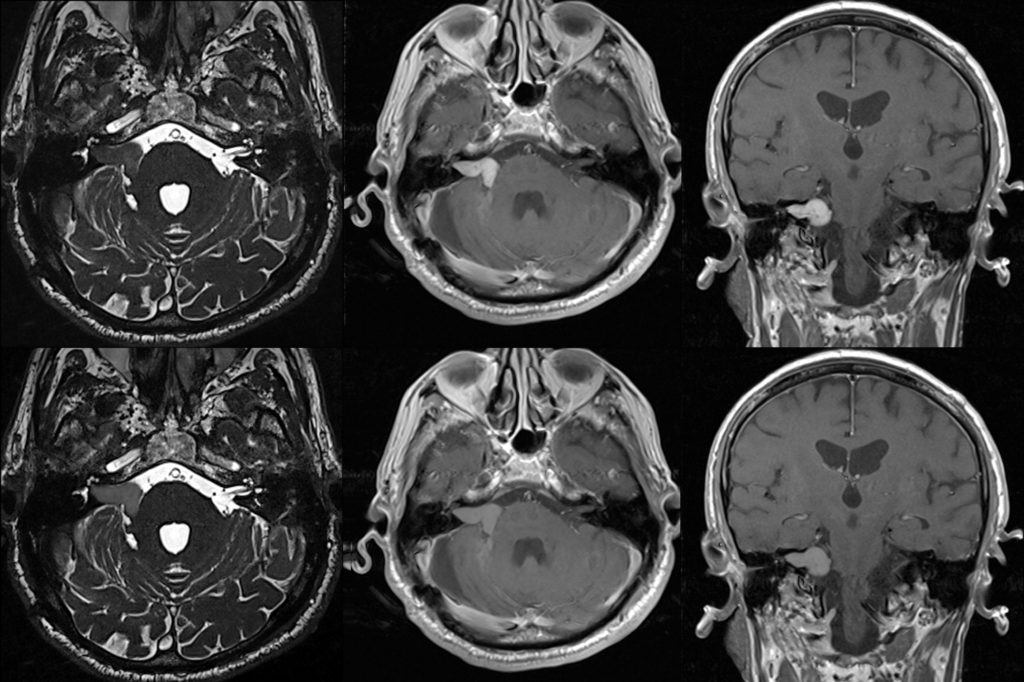

Akustikusneurinom

Vestibuläre Erkrankung Akustikusneurinom Diese Informationen sind als allgemeine Einführung in dieses Thema gedacht. Da jeder Mensch anders von Gleichgewichts- und Schwindelproblemen betroffen ist, solltest du mit deinem Arzt oder deiner Ärztin sprechen, um dich individuell beraten zu lassen. Aus Gründen der besseren Lesbarkeit wird das generische Maskulinum verwendet und auf die gleichzeitige Verwendung der Sprachformen männlich, […]